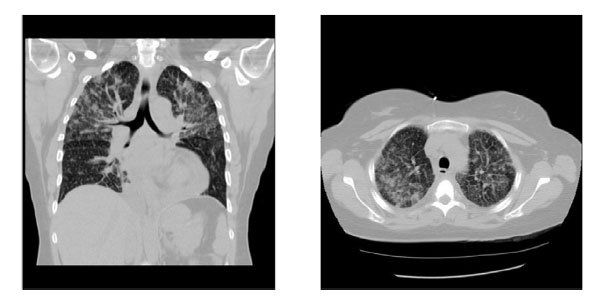

图1. CT胸部轴向(左)和冠状(右)图像

超声心动图结果表明保留的射血分数与无室壁运动异常。胸片是值得注意的弥漫性双侧浸润。因此,计算机断层摄影(CT)胸部表现出弥漫性双边融合结节和空气中的混浊与巩固的地区。基于这些发现一开始怀疑感染。进一步的住院治疗显示没有在痰和血培养物上分离出病原体。微生物学耐酸菌的涂片和培养呈阴性。其他包括自身免疫性血清学和超敏反应板也在正常范围内。

住院十二天后重复CT检查发现双肺广泛的融合性结节,左上叶和纵膈淋巴结发现集中区域(见图1)。由于病因不明的弥漫性网状结节,CT导向活检左侧进行上叶巩固。鉴于分子诊断指导临床治疗决策的重要性,对患者进行分子标志物检测结果显示表皮生长因子受体(EGFR)阳性 p.L858R突变(见图2)。